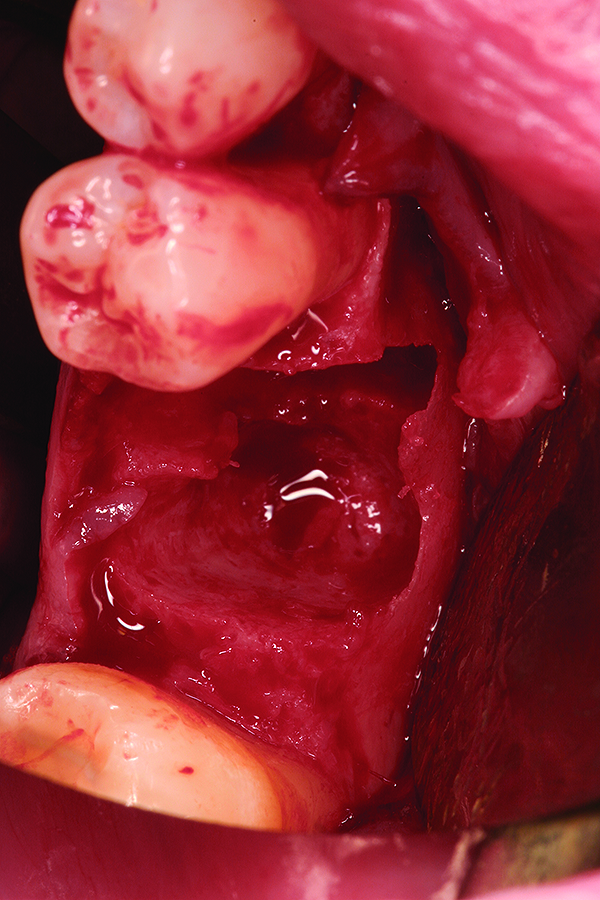

Fig 16. Note the significant dehiscence defect in the buccal wall prior to tooth extraction.

Figure 16